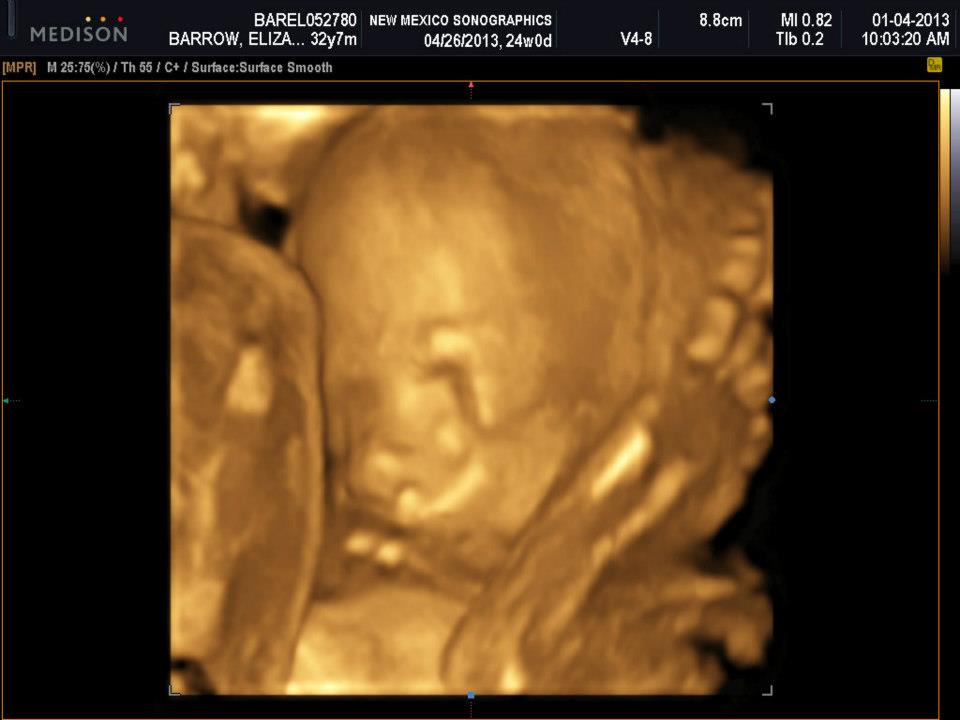

It’s weird to see her facial features. I definitely think we have a “chunker” on our hands. If you look at her cheeks, she is starting to get some fat on them. I think she is going to take after her mom with her newborn pictures. I was HUGE!

She is also has some big feet too, which we can say came from dad! There was also one picture that I can’t find where she was opening her mouth to yawn and Mike started to make raptor sounds from Jurassic Park. It was kind of creepy! I like the 3D ultrasounds, but they are a little creepy looking with the gold. But I loved, loved, loved being able to see Baby Girl doing her thing!